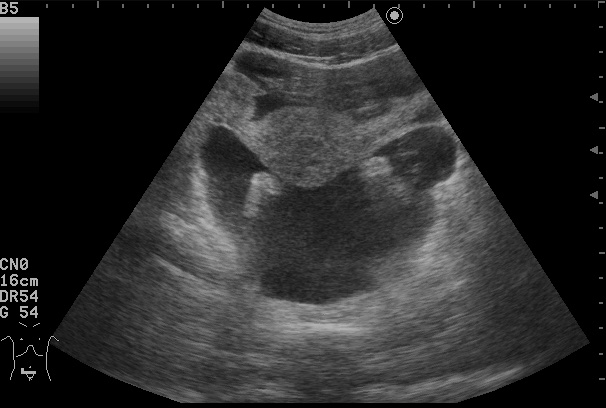

Хирург попросил выполнить разметку для дренирования асцита у женщины. Но что-то заставило рекомендовать КТ.

Что?

Где ЭТО?

Где все ЭТО, характерное для асцита?

Реальный асцит